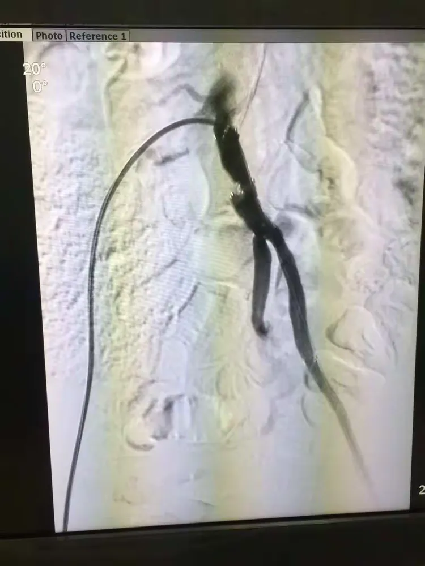

手术中,团队操作沉稳有序:导丝在闭塞血管中精准探路,球囊逐级扩张狭窄段,支架随后稳稳释放。整个过程如行云流水,医护人员配合默契,未见半分忙乱。“血流恢复了!” 监测仪器上跳跃的数据,宣告着双侧“生命线”的重建成功。

患者李大爷(化名)因“双下肢动脉硬化闭塞”导致双腿持续冰冷、酸胀,行走困难长达两年。影像检查显示,其左髂动脉完全闭塞,右髂动脉重度狭窄,病情严峻。